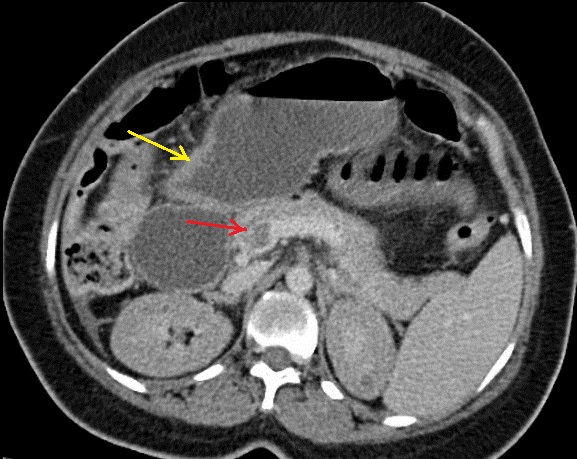

Même cas en coupe

axiale de TDM en phase arterielle . Fleche

rouge est image a íso-dense d'une thrombus de artere

mesenterique superieure . Aspect de fine de la paroi

de l'intestin se voyait encore sur cette coupe . |